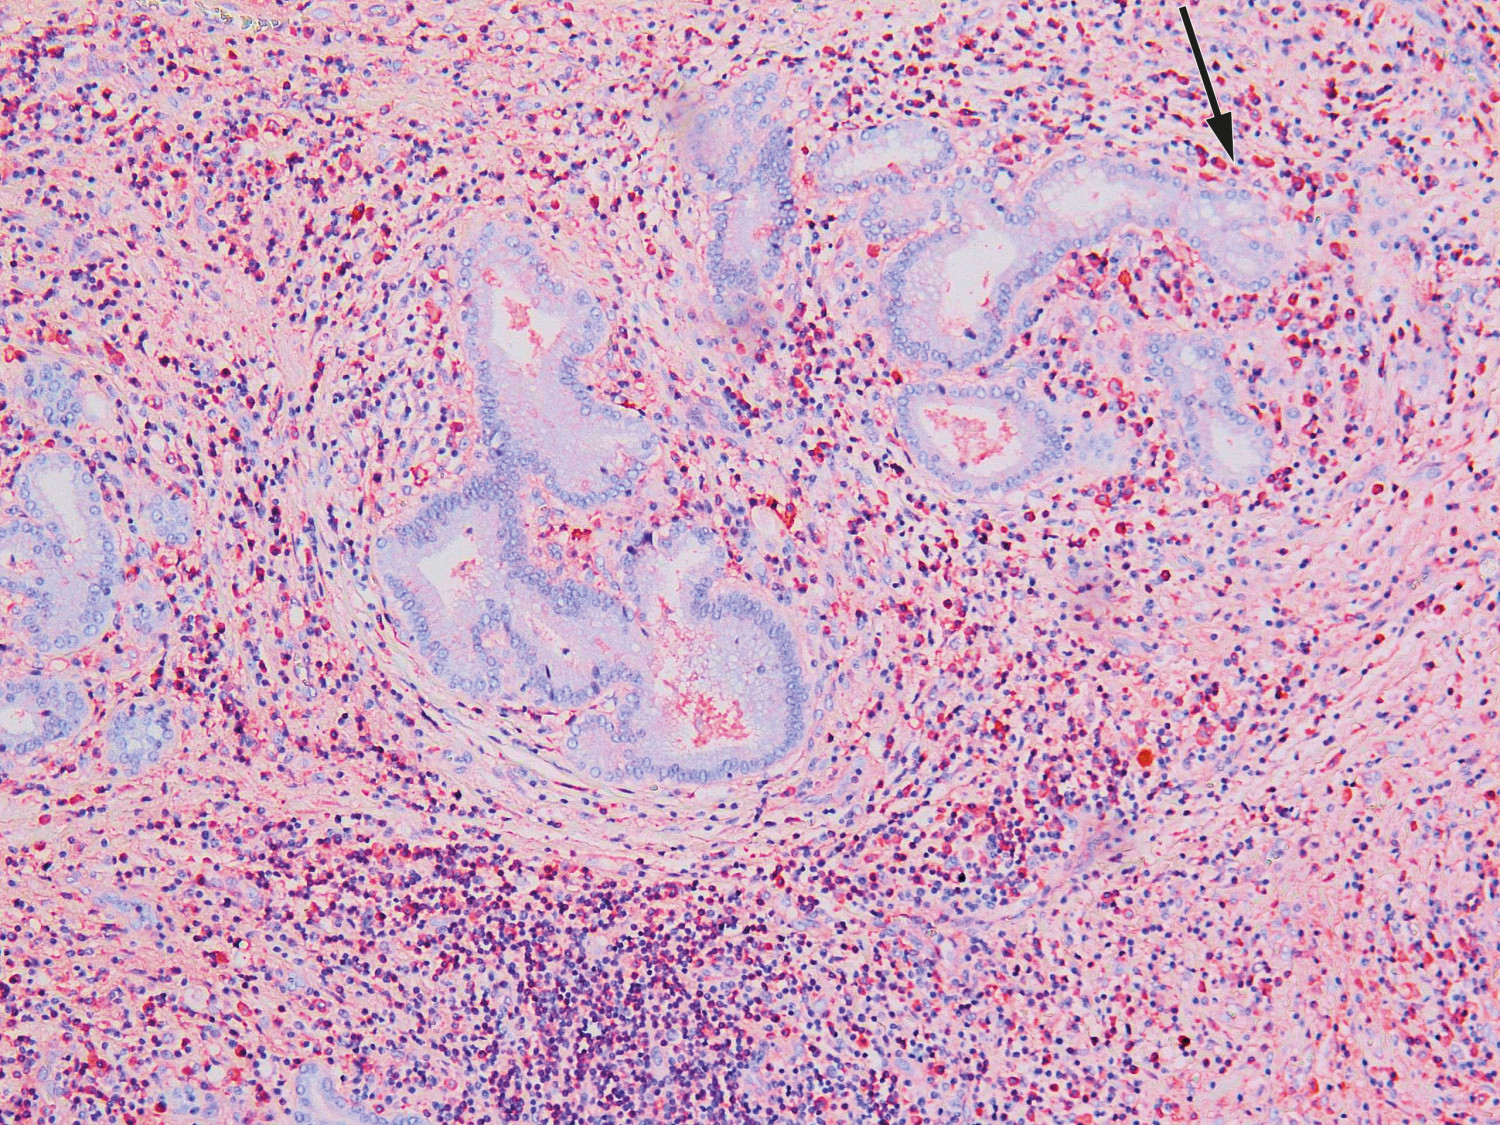

Seks dager etter overflytning ble det utført utvidet høyresidig leverreseksjon med hepatikojejunostomi. Postoperativt utviklet pasienten leversvikt med påfølgende iskemisk nekrose i gjenværende levervev. Tilstanden ble bedømt som meget alvorlig med liten sjanse for spontan bedring. Reseksjonspreparatet ble derfor undersøkt som cito-prøve i tilfelle tilstanden skulle være benign og dermed tillate transplantasjon. Histologisk prøve fra leverhilum viste ikke tegn til malignitet, men lymfoplasmacytære infiltrater og rikelig med eosinofile granulocytter. Immunhistokjemisk undersøkelse påviste overvekt av IgG4-positive plasmaceller og forhøyet IgG4/IgG-ratio på over 0,4 (figur 2). Serum-IgG4-prøve ble tatt postoperativt og var forhøyet på 6,0 g/l (0,03–2,01 g/l). Funnene var forenelige med IgG4-relatert sykdom.

Typiske funn i vevsbiopsi med lymfoplasmacytær betennelse, storiform fibrose og et forhold mellom IgG4- og IgG-positive plasmaceller på over 0,4 ved immunhistokjemisk undersøkelse regnes som gullstandard, men diagnosen må stilles ut ifra en kombinasjon av radiologiske, patologiske og serologiske funn (6). De mest kjente diagnostiske kriteriene er HISORt-kriteriene (histology, imaging, serology, other organ involvement og response to steroid therapy), som ble utarbeidet for diagnostikk av autoimmun pankreatitt og senere modifisert for IgG4-relatert skleroserende kolangitt (7).